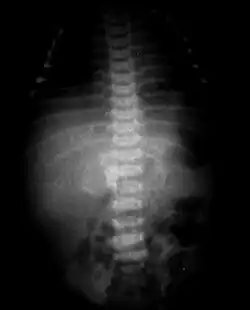

Radio de l'abdomen chez un nouveau-né. Le squelette fœtal est reconnaissable en avant des deux premières vertèbres lombaires (squelette du crâne à gauche et des fémurs à droite.

Un fœtus in fœtu ou fetus in fetu, (FIF) est une anomalie du développement de l'embryon au cours de laquelle un fœtus se trouve inclus à l'intérieur du corps de son jumeau, pouvant donner lieu au développement d'un tronc, d'organes, de membres à l'intérieur du fœtus-hôte. Cette anomalie concernerait 1 sur 500 000 bébés nés vivants[1],[2].

Il est possible que certains cas répertoriés soient en fait des tératomes. A la différence des fœtus in fœtu, les tératomes ont un potentiel de croissance indépendant et peuvent dégénérer en tumeur maligne. Un bon moyen de différencier ces deux entités est la présence d'une colonne vertébrale, habituellement absente dans les tératomes[3].